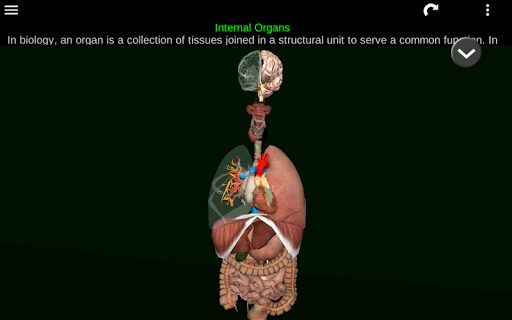

Toont een 3D-anatomisch model van de belangrijkste organen van het menselijk lichaam en een beschrijving van elk orgaan.

Wat zit er in de app?

* Spijsverteringsstelsel, inclusief de maag, dunne darm, dikke darm, en een animatie van dit systeem.

* Ademhalingssysteem, inclusief de luchtpijp, bronchiën, longen en een animatie van dit systeem.

* Voortplantingssysteem, dat de mannelijke en vrouwelijke voortplantingsorganen omvat.

* Hersenen, waaronder de hersenen, het cerebellum en de hersenstam vallen.

* Hart, dat de atria, ventrikels, aorta en een animatie van dit orgel omvat.

* Gemakkelijk te openen en te navigeren (zoom, 3D-rotatie).

* Beschrijvingen van elk orgel.